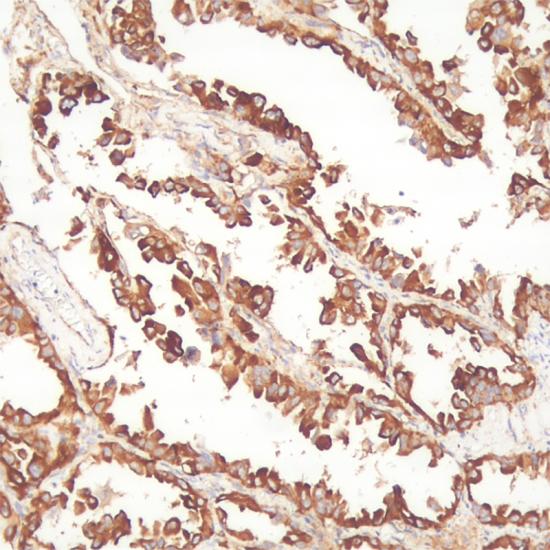

LRP抗體試劑(免疫組織化學(xué)) 閩廈械備20180131號(hào)

• 陽(yáng)性部位:

細(xì)胞漿

• 陽(yáng)性對(duì)照:

肺腺癌

肺癌耐藥蛋白LRP的分子量為110kDa,主要通過(guò)核與細(xì)胞漿間藥物轉(zhuǎn)運(yùn)障礙,或藥物進(jìn)入胞質(zhì)囊泡成房性分隔使靶點(diǎn)藥物有效濃度下降而產(chǎn)生耐藥。LRP所介導(dǎo)的是P糖蛋白和MRP不能介導(dǎo)的烷化劑、鉑類的耐藥,對(duì)臨床化療藥物的選擇具有指導(dǎo)意義。